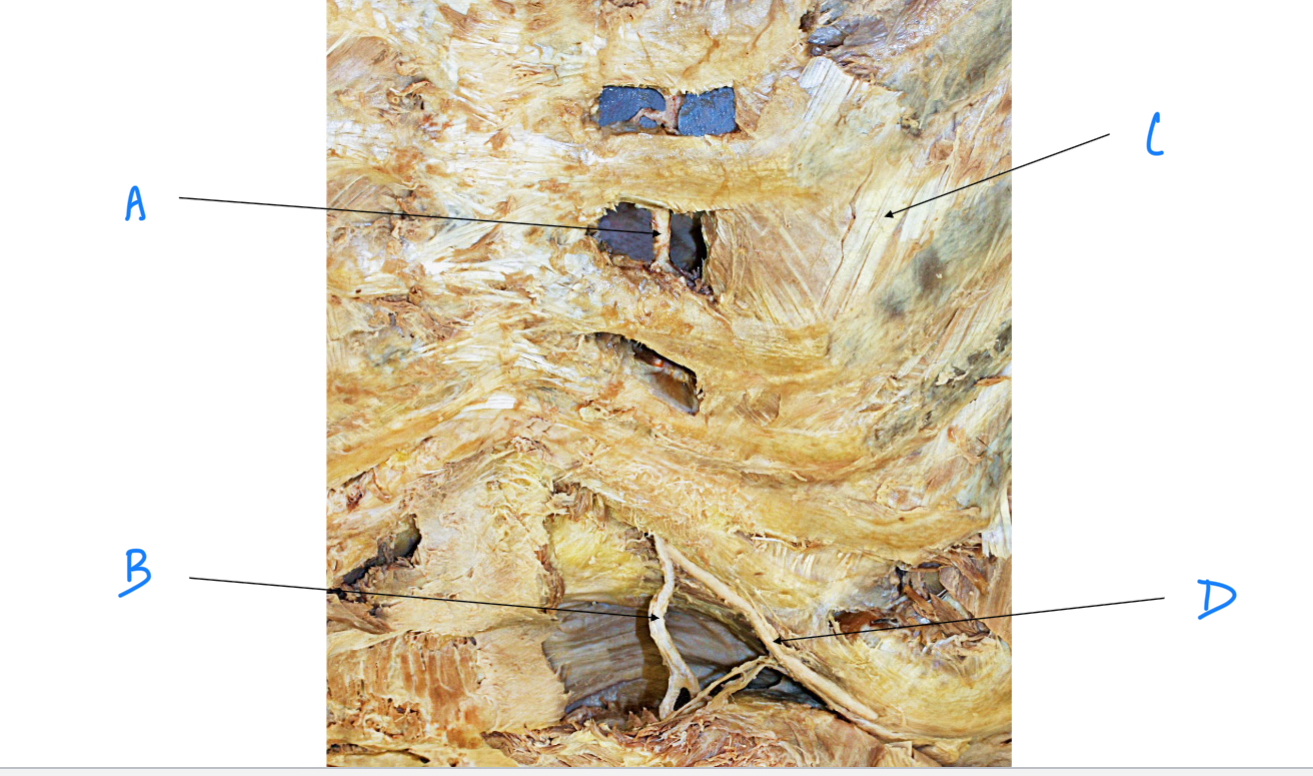

A. Identify structure

Transverse foramen; Vertebral a.

B. Identify structure; What goes through this feature?

Transverse process

C. Identify structure